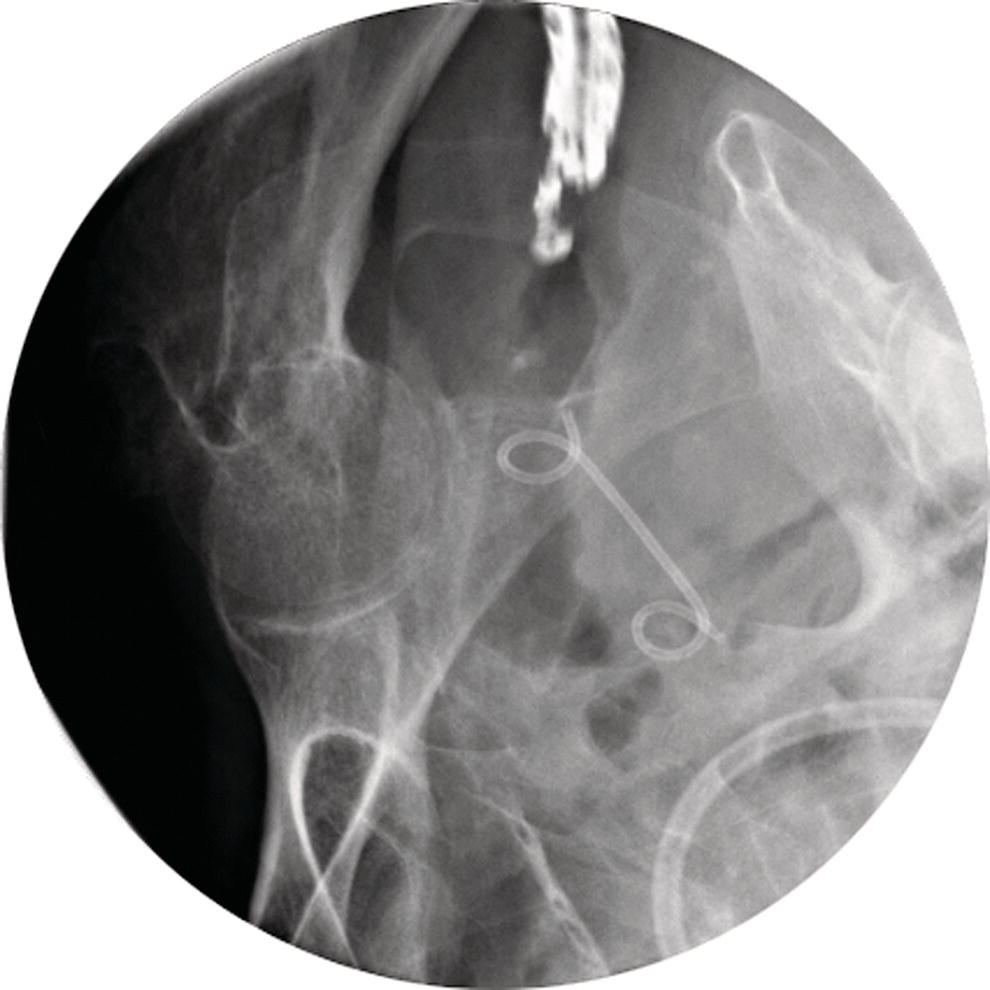

From radiologykey.com

How to do EUS‐guided Pelvic Abscess Drainage Radiology Key What Is An Abscess Drainage Learn how to manage skin abscesses, including incision and drainage, antibiotic therapy, and indications for parenteral. Find out the risks, benefits,. Learn what an abscess is, how it is diagnosed and treated, and what to expect after an incision and drainage procedure. An abdominal abscess is a pocket of pus and infected fluid in your belly caused by bacterial infections.. What Is An Abscess Drainage.